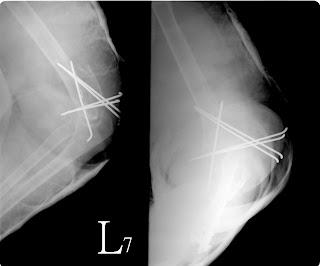

二十八歲的「席多金」肺不舒服,經常咳血。到醫院檢查,肺裡有異物。照了X光,醫生研判是腫瘤。昨天,開刀割瘤。結果發現,在「席多金」肺裡作祟的竟然是一棵五公分高的小松樹。